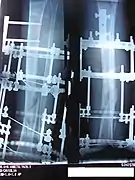

The photographs and radiographs illustrate the application and emplacement of an external fixator, an Ilizarov apparatus, to repair the open fracture of the lower left leg of a man. The photographs were taken four weeks after the patient fractured the shinbone (tibia) and the calfbone (fibula) of his left leg, and two weeks after the surgical emplacement of the Ilizarov apparatus to immobilise the leg and isolate the wound and fracture site to facilitate healing.

- X-ray of the fracture site and the emplaced apparatus, two months post-fracture; perspective 1-4.

- X-ray of the fracture site and the emplaced apparatus, two months post-fracture; perspective 2-4.

- X-ray of the callus forming at the fracture site, three months post-fracture; perspective 3-4.

- X-ray of the callus forming around the fracture site, three months post-fracture; perspective 4-4.

- X-ray perspectives of the callus-formation progress and healing of the fractured tibia and fibula bones, four months post-fracture.